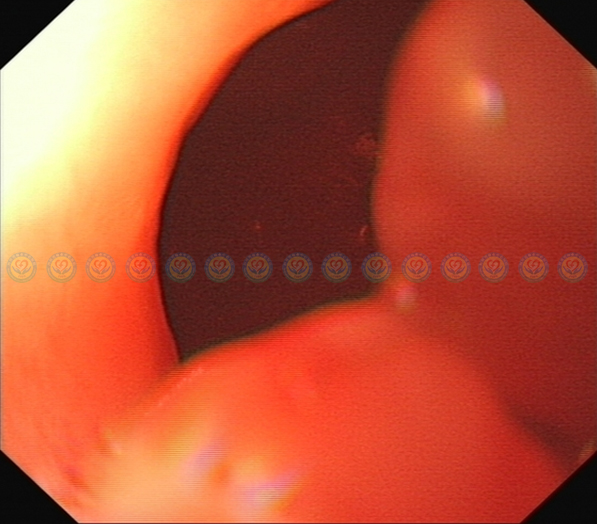

精细操作胃镜,进入幽门,见肿块大部分位于十二指肠球部